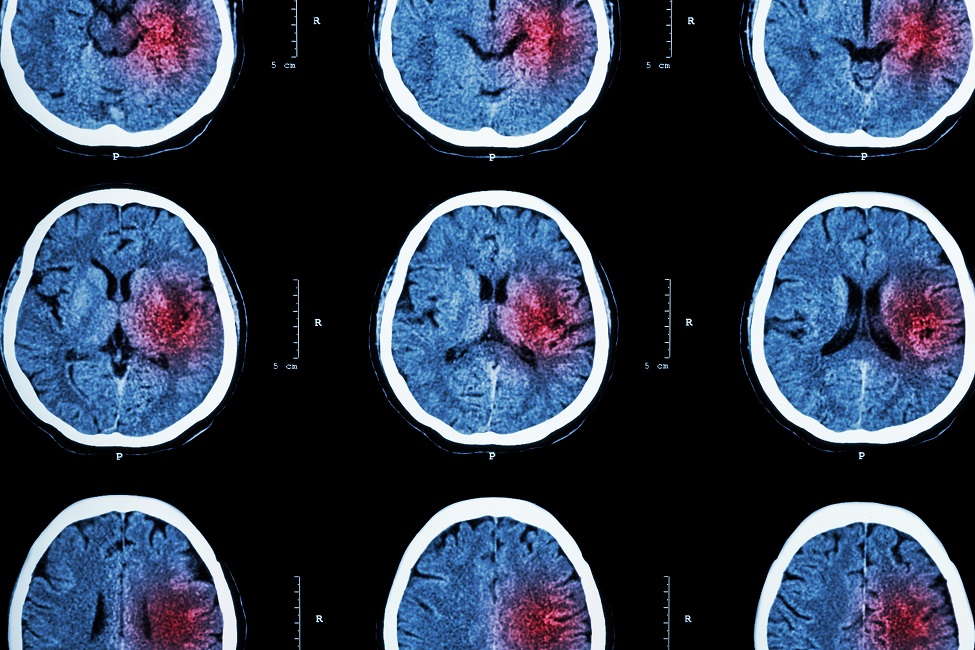

Nearly 800,000 people have a stroke each year and about 87 percent are ischemic strokes, where blood flow to the brain is constrained or clogged.

Stroke is the third leading cause of death and disability in the United States, with one person dying every four minutes. Nearly 800,000 people have a stroke each year and about 87 percent are ischemic strokes, where blood flow to the brain is constrained or clogged. While there have been significant strides made in stroke research as well as major advances in stroke care, effective treatments are still insufficient and require a continued quest for new remedies. Current drugs designed for stroke intervention and treatment are based on their anti-oxidative properties or blockers of calcium channels or glutamate receptors. However, no clinically effective therapeutic intervention for stroke has yet been developed.